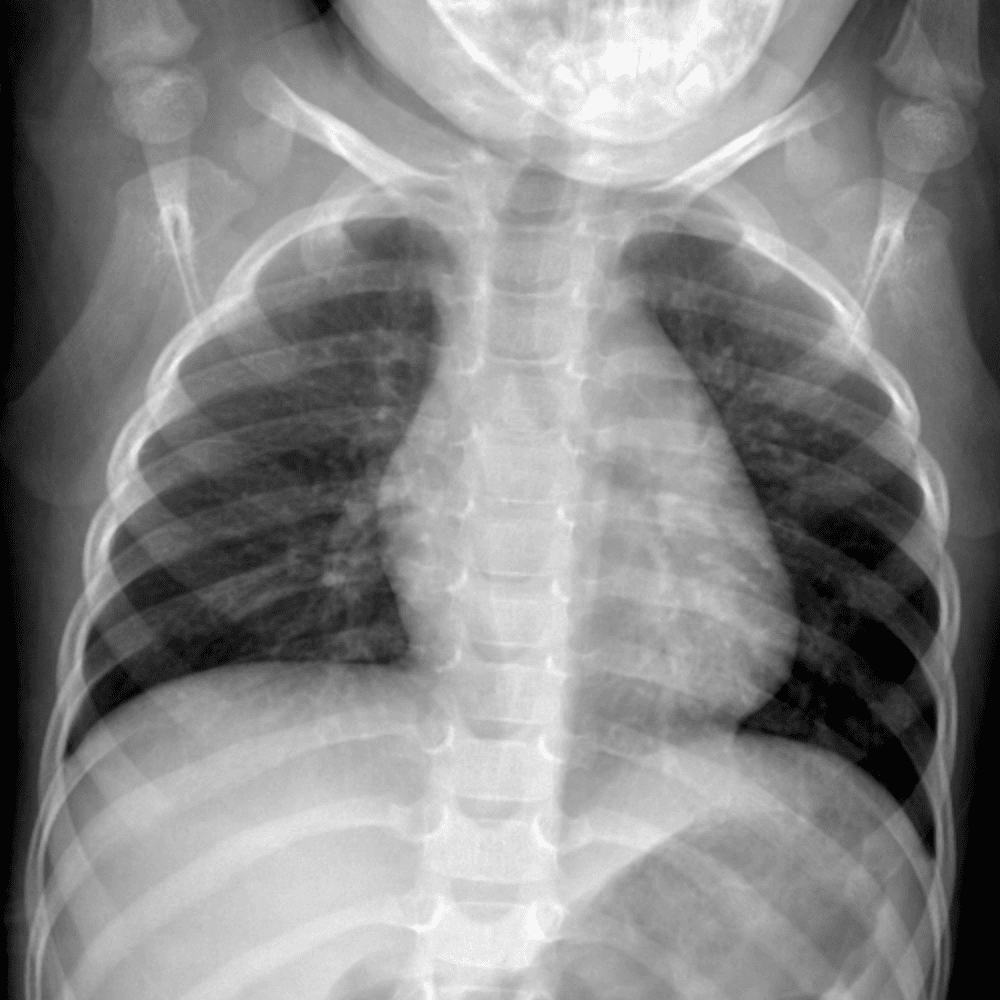

Peds Chest

Practice

Simulates call by including subtle or difficult cases and some normals.

50 cases